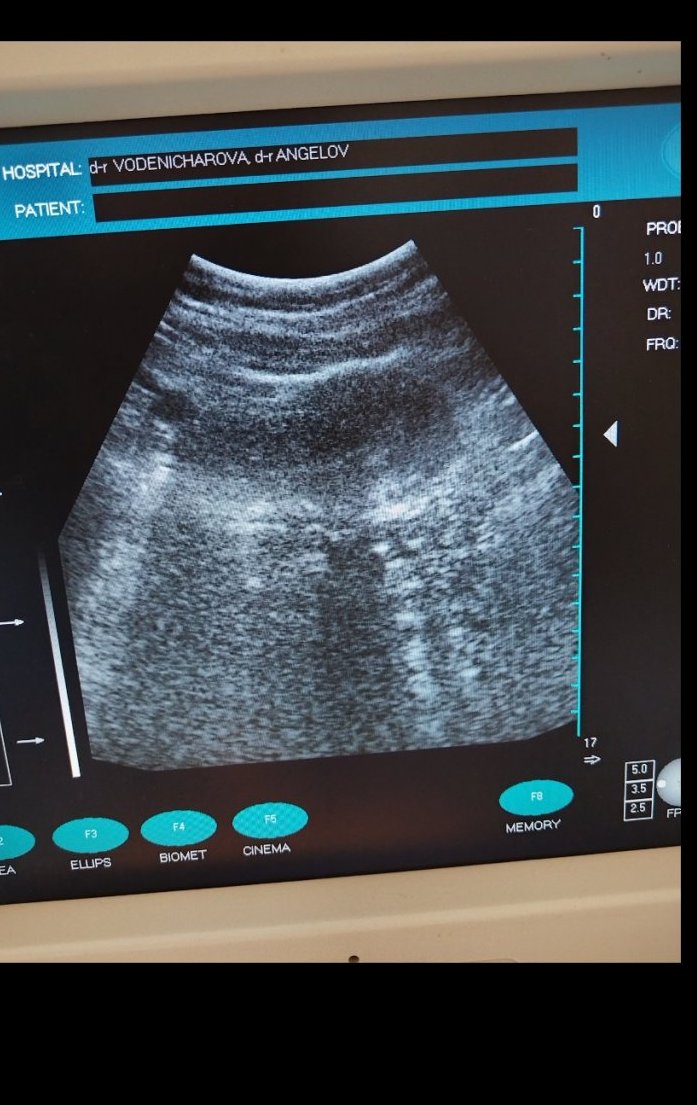

Извънматкова бременност възниква, когато оплоденото яйце се имплантира извън матката, обикновено в една от фалопиевите тръби. Симптомите могат да включват едностранна коремна болка, вагинално кървене и дискомфорт по време на уриниране или дефекация. При извънматкова бременност нивата на ЧХГ може да не се повишат както обикновено или дори да намалеят. Това е сериозно състояние, което изисква незабавно медицинско внимание, така че е важно да се консултират с лекар при съмнение за извънматкова бременност. Извънматковата бременност е състоянние, при което оплоденото яйцеклетка се имплантира извън матката, обикновено в една от фалопиевите тръби. Симптомите включват коремна болка, кървене и нерведен менструален цикъл. Това е спешно медицинско състояние, което изисква незабавно лечение. Извънматковата бременност е състоянние, при което оплоденото яйце се имплантира извън матката, обикновено в една от фалопиевите тръби. Симптомите включват коремна болка, вагинално кървене и нисък ЧХГ може да бъде показателен за това състояние. Това може да доведе до тежки медицински усложнения и изисква спешно лечение. Симптомите включват коремна болка, вагинално кървене и нива на ЧХГ под очакваните за дадената седмица на бременността.